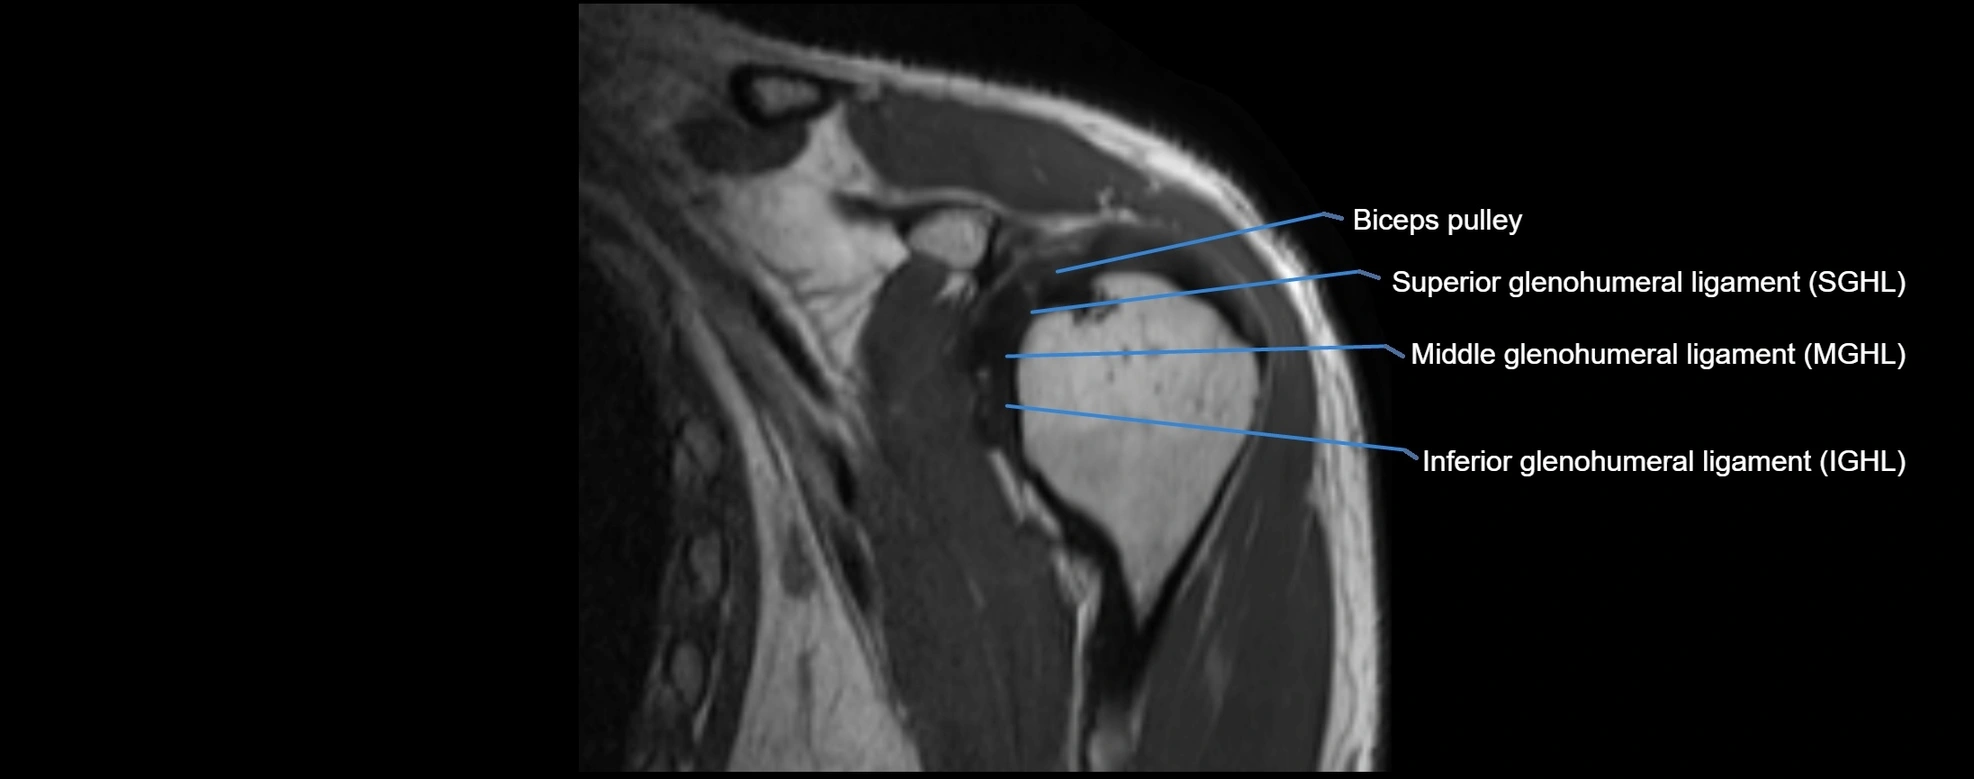

MRI images

image